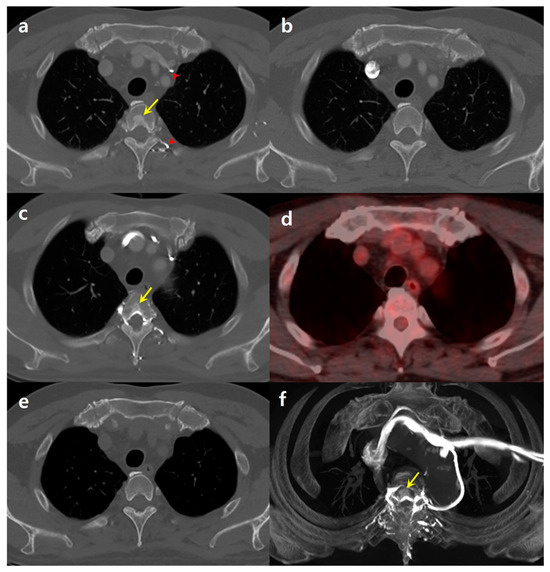

A 65-year-old male, who had successfully undergone surgery for colon cancer five years earlier, was engaged in ongoing surveillance for any signs of cancer recurrence or metastasis. Throughout this period, he maintained good health without any indications of local cancer recurrence or distant metastasis. As part of his routine follow-up, the patient underwent a chest CT scan. For this procedure, contrast material was administered through his left antecubital vein. The enhanced CT images, viewed using a bone window setting, revealed an unexpected finding: a focal sclerotic lesion located centrally in the T3 vertebral body (Figure 1a). This lesion was notably absent in a CT scan taken six months earlier, where the contrast injection had been performed on the right side (Figure 1b). There was no evidence of deep venous obstruction in any part of the patient’s body.

The patient’s medical records showed that he had undergone a total of nine chest CT scans since his operation for colon cancer. Of these, five were conducted with right-side contrast injection and four with left-side injection. Intriguingly, none of the CT scans with right-side injection showed any focal sclerotic lesions in the vertebrae. However, all four chest CT scans involving left-side injection consistently revealed a sclerotic area at the same T3 location, although the extent of the sclerotic area varied slightly (Figure 1c). Further investigations using 18F-FDG PET-CT showed no abnormalities at the same vertebra location (Figure 1d). Additionally, the sclerotic lesion was not visible in unenhanced CT images (Figure 1e). Maximum-intensity projection reconstruction of the contrast-enhanced CT images revealed a focal enhancing area in the T3 body, which was attributed to contrast reflux from the left brachiocephalic vein (BCV) through the paravertebral venous plexus (Figure 1f).

Figure 1. A 65-year-old male patient with a history of colon cancer surgery. (a) Contrast-enhanced chest computed tomography (CT) image, obtained with left-side contrast injection using bone window setting, reveals focal sclerotic area at the central portion of the T3 vertebral body (arrow). Notably, contrast arrival is observed in the left brachiocephalic vein and the left paravertebral venous plexus (arrowheads). (b) Chest CT obtained six months ago with right-side injection shows no evidence of a sclerotic lesion in the T3 vertebral body. (c) Chest CT obtained 11 months ago with left-side injection reveals the presence of focal sclerotic lesion (arrow) in the same location. (d) 18F-FDG PET-CT reveals no abnormalities in the same vertebra site. (e) A follow-up unenhanced chest CT conducted six months later from (a) shows no sclerotic lesion. (f) Maximum-intensity projection (MIP) image reconstructed from an enhanced CT reveals a focal enhancing area at T3 (arrow), with the surrounding vertebral venous plexus opacified through reflux from the left brachiocephalic vein.